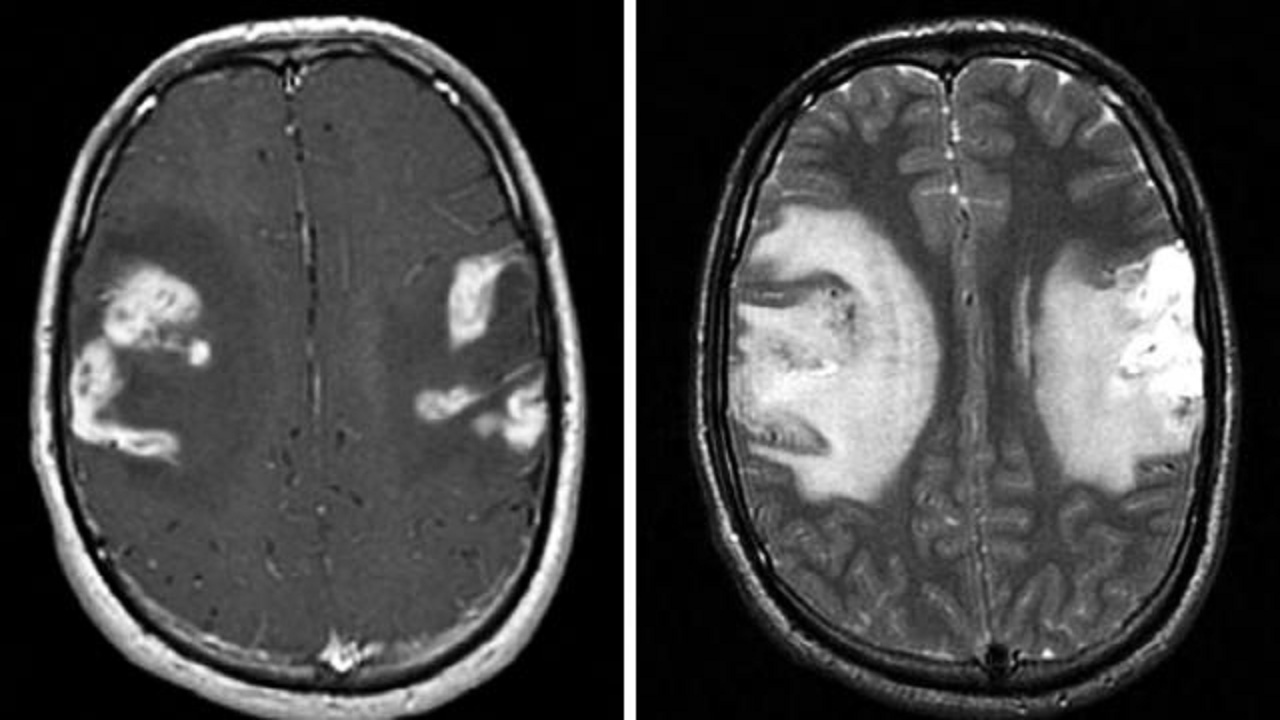

2.MRI:病变易累及双侧皮层、皮层下及深部白质。呈长或短或混杂T1,长T2信号。DWI常呈高信号,但部分患者病变中心以低信号为主。

3.HR-MRI及BB-MRI:病变出血管管壁向心性增厚强化。

4.SWI:可见微出血。